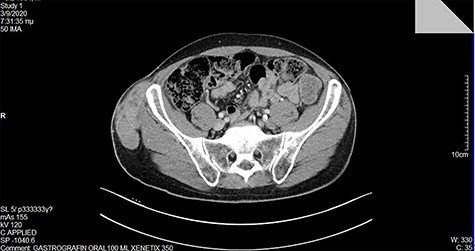

At our institution, on clinical examination, surgeons verified the swelling of the ilioinguinal aera and detected at tumescent, palpable and hard mass of the right pelvic fossa (Fig. 3). Lab examinations were unremarkable. Subsequent pelvic magnetic resonance imaging (MRI) (Fig. 4) and computed tomography (CT) scan identified a tumescent lipomatous tumor, without the presence of any metastatic lesions. Guided biopsy indicated the presence of an ilioinguinal liposarcoma located into the fatty tissue of the right iliac fossa. Following these, the interdisciplinary team decided to schedule a primary complete curative resection of the tumor (R0).